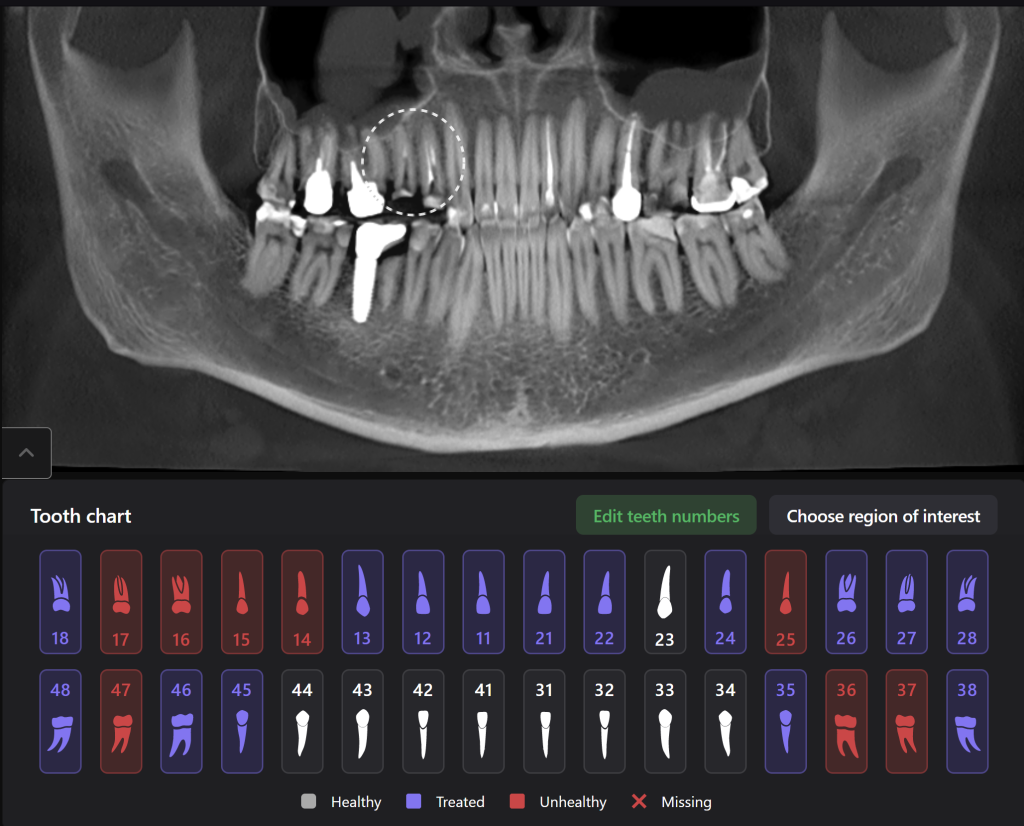

Um eine klinische Entscheidung zu treffen, analysierte der Zahnarzt die Untersuchungsdaten und den Diagnocat-Röntgenbericht. Der Bericht enthält eine Bewertung der Vorbehandlung und Informationen über das Vorhandensein von periapikaler Radioluzenz.

Man beachte die hohe Wahrscheinlichkeit, die Diagnocat anzeigt. Es wurde entschieden, die Zähne zu erhalten und eine endodontische Behandlung durchzuführen.